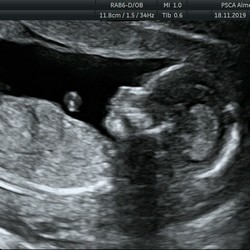

Ik ga begin augustus een spiraal laten zetten, ik ken zat vrouwen die er 1 hebben en geen een heeft er iets negatiefs over dus ik heb er wel vertrouwen in. Bij mij doet de verloskundige het doormiddel van een echo.